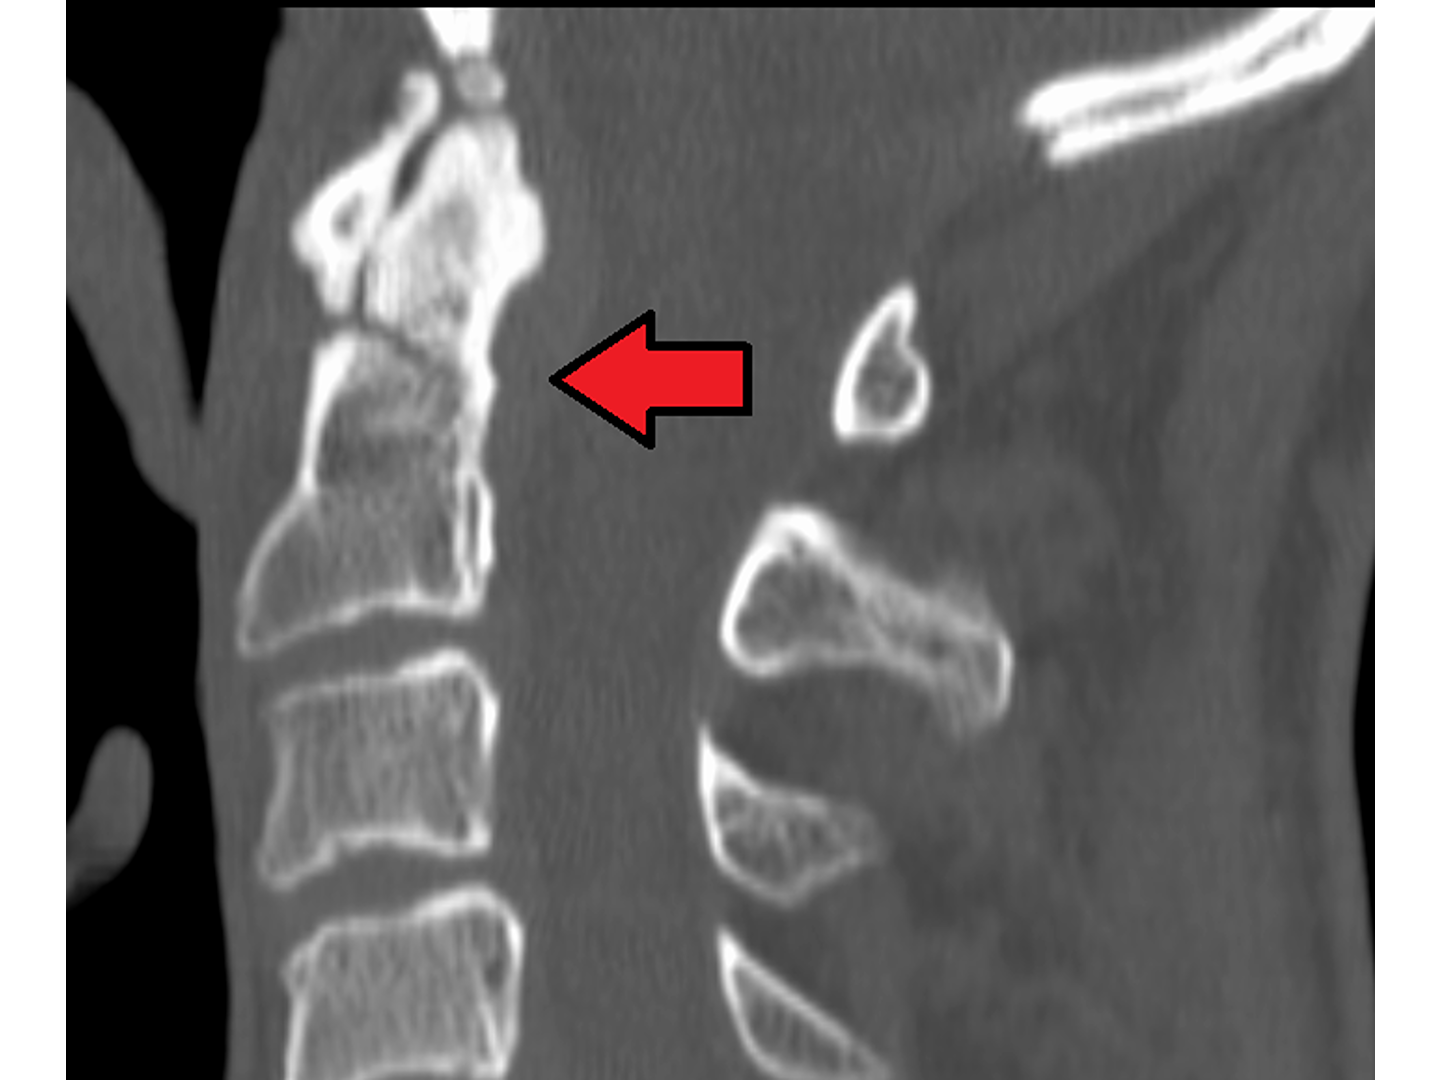

Verursacht wird sie durch ein Hyperextensionstrauma. Eine weitaus häufigere Ursache als das Erhängen sind Autounfälle, bei denen der Kopf eines unangeschnallten Fahrers frontal auf das Lenkrad schlägt. Siehe [[Abb. 789]] & [[Abb. 790]]